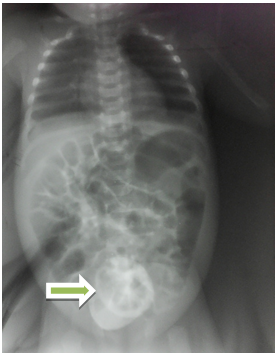

Low digestive opacification objectived a long and small pertuis of third proximal transverse colon through which the contrast product passes associated with a dilation of the colon segment upstream of the lesion and a smaller downstream colon (Figure 4). During evacuation, occurring 5hours after the beginning of the examination, a stop image is noted in a concave cup downstream of the contrast product (Figure 5). We noted presence of colonic austration in the recto-sigmoid region and no abnormal length of colon.

Figure 5 "Wind-sock" sign: image of stop in concave cup downstream during evacuation (green arrow).

two orders of arguments, considered as pathognomonic of type I colic atresia were noted : Presence of a long and small pertuis of third proximal transverse colon through which the contrast product passes associated with dilation of the colon segment upstream of the lesion and a downstream colon of smaller size. These images correspond to the type I of the colonic atresia according to LOUW that is defined by a complete mucous diaphragm obstructing the intestinal lumen, without interrupting sero-muscular and externally by a disparity of caliber. The second sign is an image of stop in concave cup downstream of contrast product, during evacuation corresponding to the "Wind-sock" sign described by BLANK and collaborators.2